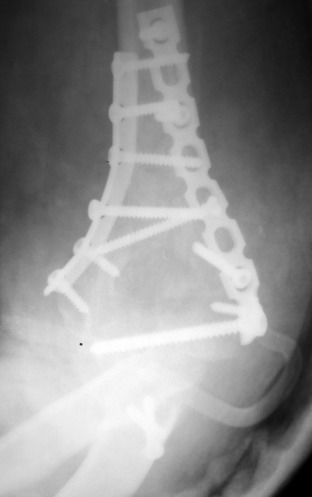

Примерный случай, только перелом был открытый, в задне-медиальной стороне рана около 2 см по характеру "изнутри кнаружи", неврологический статус со слабостью сгибания мизинца, также слабая абдукция и аддукция указательного пальца и сгибания в кисти.

Больному сделали обработку и наложили временный аппарат внешной фиксации плечо-предплечье.

На шестой день сделали открытую репозицию чрезлоктевым доступом двумя locking plate, локтевой нерв был ушибленным, после операции положительная динамика в Flexor Carpi Ulnaris. Фиксацию локтевого отростка произвели tension band technique с дополнительным шурупом.

Этапы операции на снимках....

Джолдас Кульджанов

Djoldas Kuldjanov, MD

Department of Orthopedic Surgery

St. Louis University Medical Center